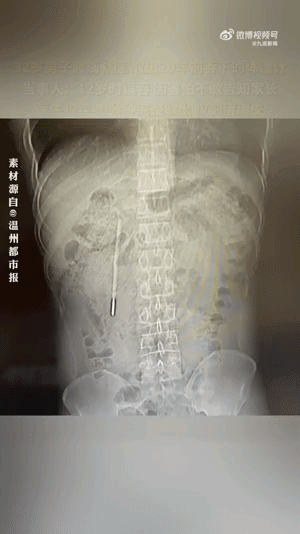

12岁误吞体温计32岁时取出,男子腹痛取出20年前吞的体温计:12岁时误吞,因害怕不敢告知家长】32岁的王先生最近腹部消化不好,前往温医大附一院龙港院区就诊。该院区医生对其做腹部CT检查,发现其十二指肠处有异物,高度怀疑是水银体温计,前端已抵在肠壁上,随时可能引发穿孔、大出血等严重后果。追问病史后得知,这根体温计是王先生12岁时不慎误吞的,当时因害怕不敢告知家长,其家长忙于工作疏于看管,而王先生的身体也没出现异样,也就没把此事放在心上。该院内镜中心医护团队立即开展内镜下取物操作。由于体温计滞留时间长、位置深,且毗邻胆管胰管,操作空间狭窄,稍有不慎便会损伤肠壁。团队在相应器械的辅助下精准定位,用圈套器套住体温计一端,缓慢轻柔提拉,仅用20分钟便成功将其完整取出,取出的体温计除刻度消失外,外观完好无损。